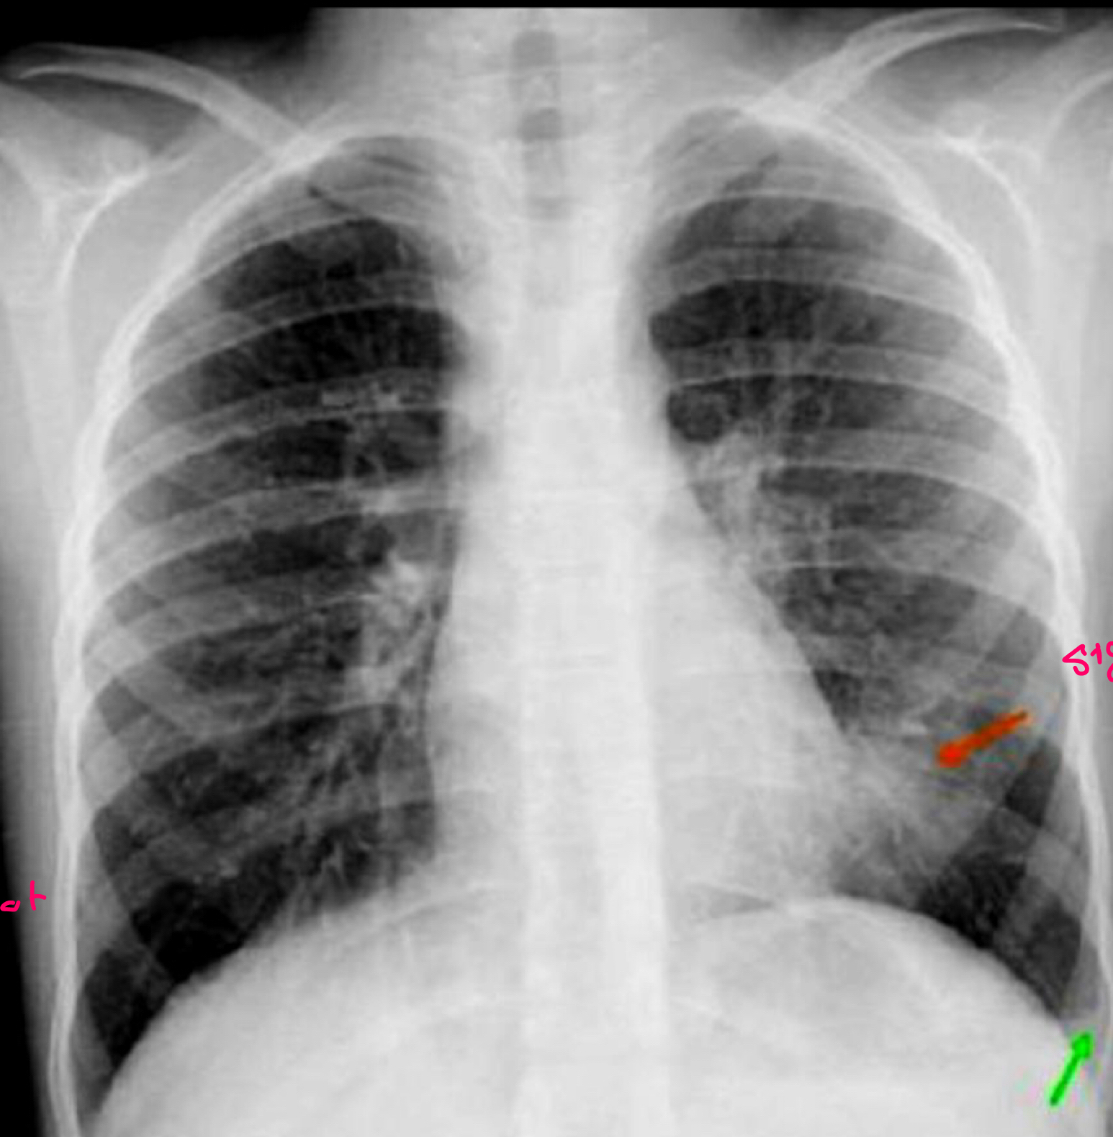

para q sirve la imagen aquí

no hace Dx solo apoya

como sale en las RX de 75% de px

normales

q se ve en RX

patrón hiperclaridad e hiperinsuflacion

Engrosamiento bronquial

Q se ve

Rojo: signo de corazón peludo

Verde: líneas kerly